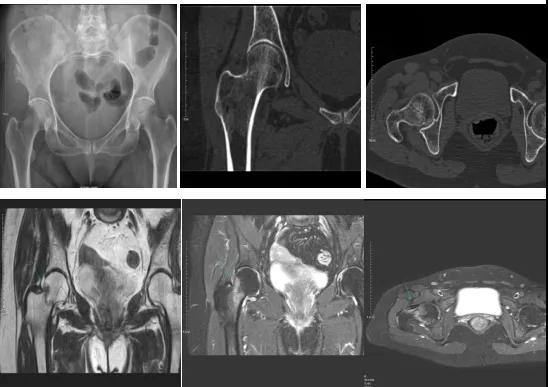

DR示:右側(cè)股骨頸未見(jiàn)明顯骨折征象。CT右側(cè)股骨頸骨質(zhì)密度不均?;颊唧w征明顯,為明確診斷,行MRI檢查。MRI示:右側(cè)股骨頸T1WI呈低信號(hào),脂肪抑制序列呈高信號(hào);提示右側(cè)股骨頸隱匿性骨折。

2.CT或MRI檢查。CT是斷面成像,不會(huì)出現(xiàn)重疊而導(dǎo)致漏診,同時(shí)CT還可以進(jìn)行多平面的重建,除了發(fā)現(xiàn)X線無(wú)法發(fā)現(xiàn)的骨折外,還可以三維直觀的顯示骨折的程度,對(duì)臨床治療有指導(dǎo)意義。CT無(wú)法發(fā)現(xiàn)骨裂、不全骨折或者骨挫傷,對(duì)軟組織的損傷診斷也有局限性,MRI就可以發(fā)現(xiàn)這些損傷。

隱匿性骨折是一種假隱性現(xiàn)象,CT、MRI、核素骨顯像有助于隱匿性骨折的診斷,各有優(yōu)劣,應(yīng)合理選擇。